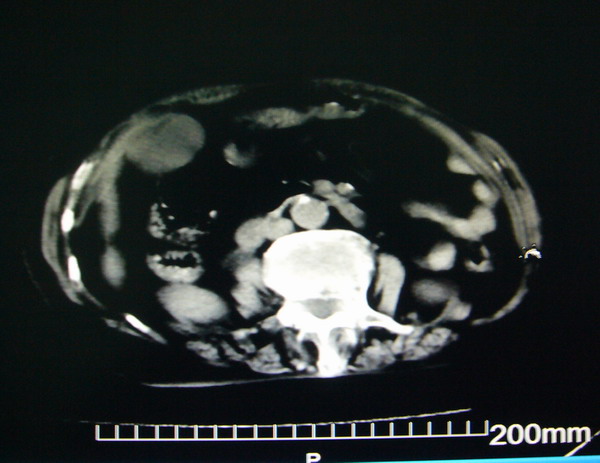

女:83y,转移性右下腹痛2小时,白细胞计数增高。

1.右侧肾盂扩大,肾盏无扩张,考虑:先天性肾盂变异可能性大。

2.胆囊扩张,考虑:胆囊炎。

3.阑尾区域可见以结节样高密度影,结合病史,考虑:阑尾结石,阑尾炎。

右下腹肠系膜增厚,结合病史支持阑尾炎.

右侧壶腹型肾盂可能,建议输路造影或增强

1.右侧肾盂扩大,考虑先天性肾盂变异或肾盂旁囊肿。

2.胆囊扩张,考虑胆囊炎。

3.阑尾区域可见结节样高密度影,结合病史考虑:阑尾结石、阑尾炎。